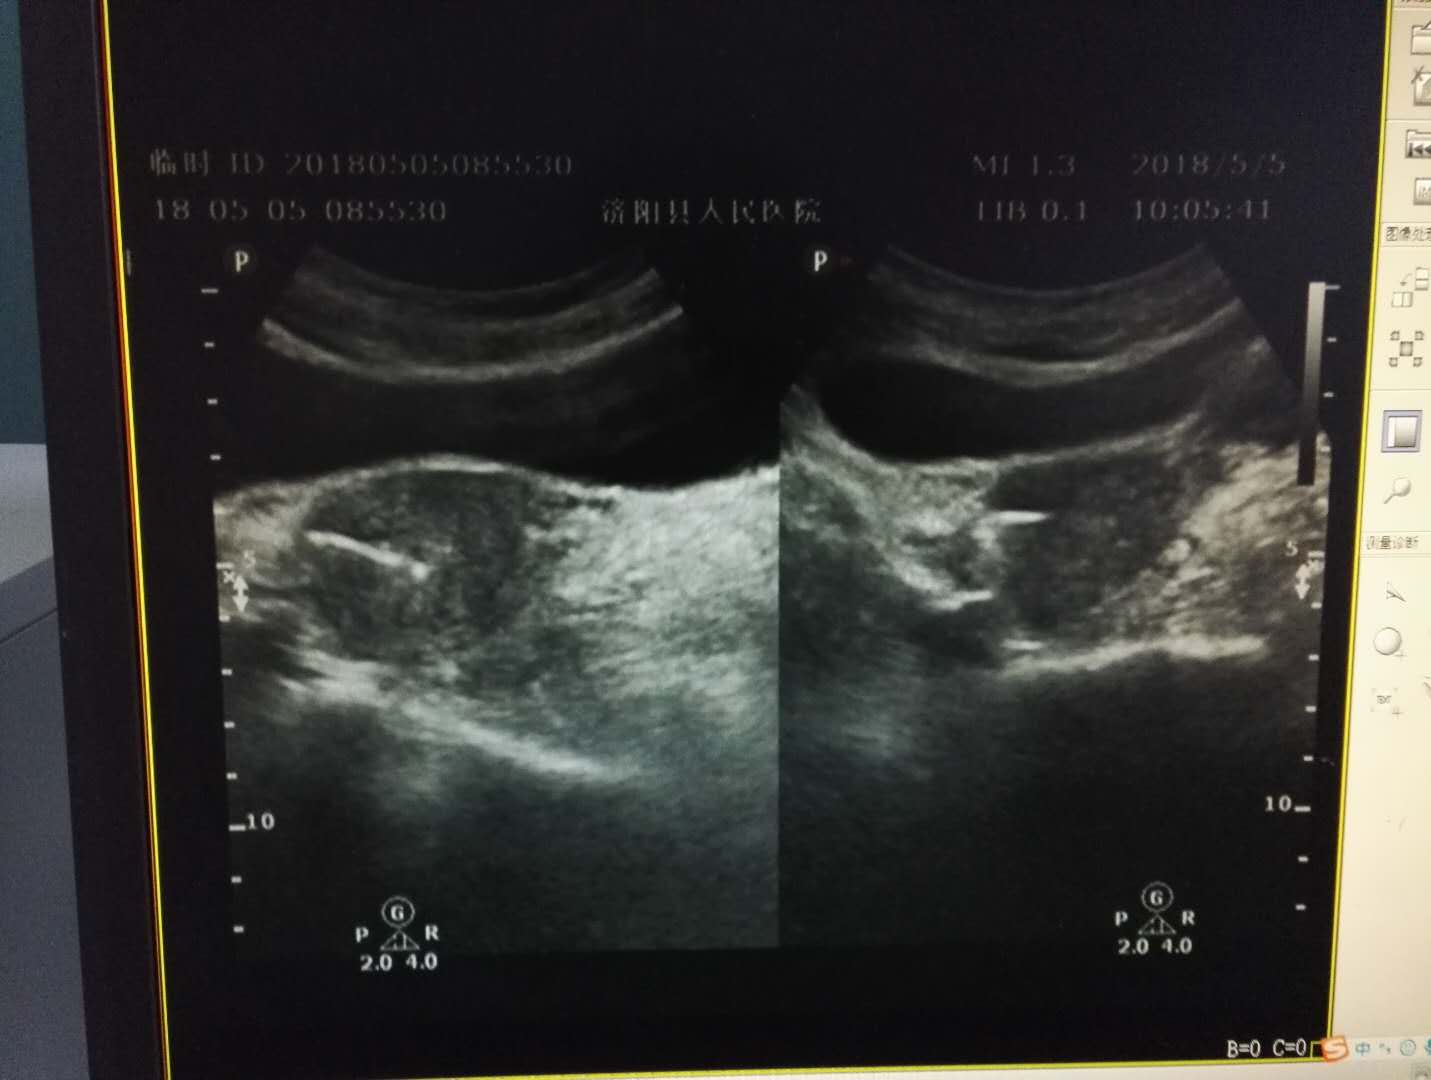

李女士根据妇科医生建议来到超声室,超声大夫也是第一次碰到这种案例,经过科室会诊后,诊断李女士为节育器宫底肌层嵌顿并部分穿破子宫向外延伸至膀胱壁,也就是说李女士的“环环”就是个不安分的“环环”。随后,李女士住院进行了节育器取出术加膀胱修补术,“环环”直接被请出了宫……